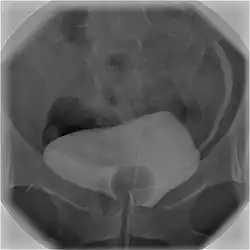

![]() Cystography image showing contrast in the urinary bladder and left ureter (right side of image). | |

In radiology and urology, a cystography (also known as cystogram) is a procedure used to visualise the urinary bladder.

Using a urinary catheter, radiocontrast is instilled in the bladder, and X-ray imaging is performed. Cystography can be used to evaluate bladder cancer, vesicoureteral reflux, bladder polyps, and hydronephrosis. It requires less radiation than pelvic CT, although it is less sensitive and specific than MRI or CT. In adult cases, the patient is typically instructed to void three times, after which a post voiding image is obtained to see how much urine is left within the bladder (residual urine), which is useful to evaluate bladder contraction dysfunction. A final radiograph of the kidneys after the procedure is finished is performed to evaluate for occult vesicoureteral reflux that was not seen during the procedure itself.[1]